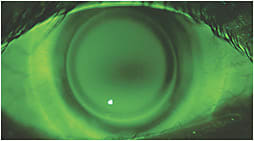

In the United States, more modern hybrid lenses designed for normal eyes do not need fluorescein to assess their fit (Figure 1). Conversely, hybrid lenses designed to vault over irregular corneas do require fluorescein to be dipped into the preservative-free saline that fills the bowl of the lens prior to lens application (Figure 2). For these cases, regular-weighted fluorescein will work without staining the soft skirt due to the silicone hydrogel materials used.